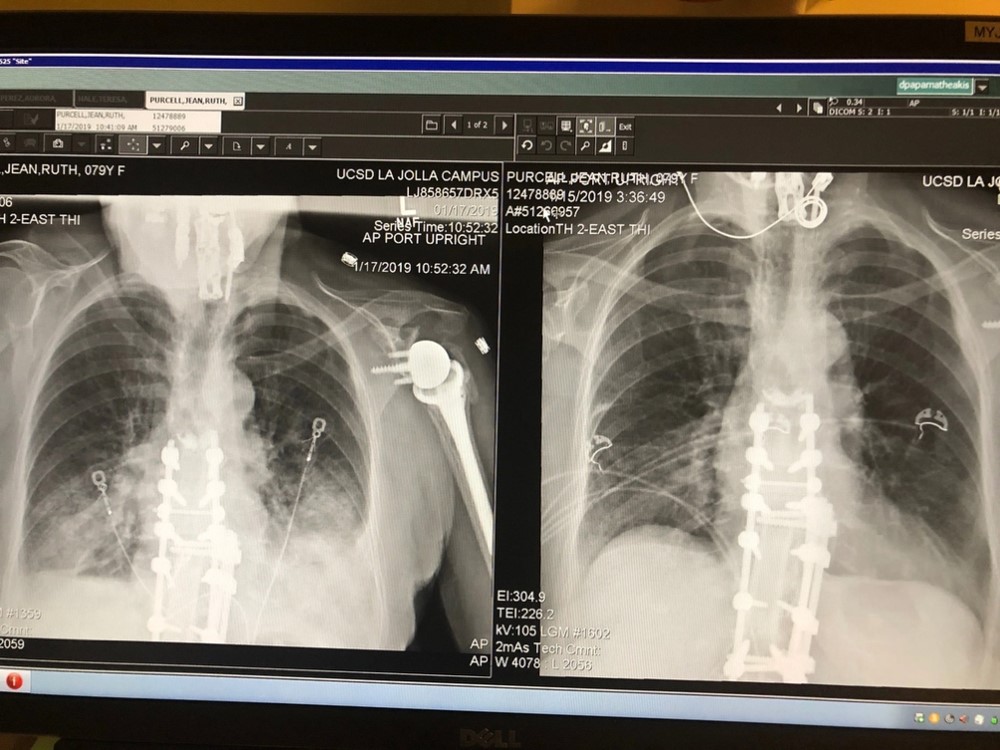

Years ago I had a limited understanding of why people fall and how horrible the results could be until my wife Jean began to have balance problems and fell often. I wanted to understand why this was happening in layman’s terms. One time Jean was hospitalized for almost six months. Over the years, I learned a lot about the medical reasons for Jean’s [and other people’s falling ] that gave me a better understanding of the causes and outcomes for our loved ones after they have a fall.  What Jean and I went through, and my responses to try to help her and others eventually led to the inventions of the upright walker and men’s bedside urinal. I’ll explain why. [ X-Ray photo above is of Jean’s spine and shoulder ]

Jean was falling a lot. The results of her falls were terrible: concussions, broken  bones, bleeding, bruising and ultimately I am convinced, brain injury. After many surgeries, when visiting a neurologist, he said the principal problem was her spine.  Her orthopedic doctor said it was not and had done many spine surgeries on Jean. He said that it was neurological. It was frustrating for everyone, so her ortho doc referred Jean to Mayo Clinic where we went for thorough tests. Mayo Clinic is extraordinary, they practice a different kind of medicine there, rapid testing, appointments lined up for every hour, everything comprehensive and well planned ahead of a visit. It was an amazing experience. We stayed at a hotel attached by tunnels to different buildings in the complex and were constantly on the move between tests and doctors.